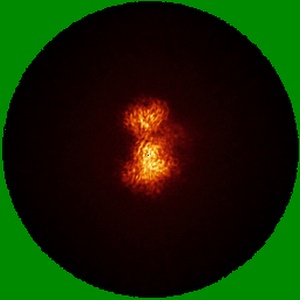

CryoEM structure of non-neutralizing bivalent antibody CBH-4B in complex with Hepatitis C virus envelope glycoprotein E2

Cryo-EM structures of HCV E2 glycoprotein bound to neutralizing and non-neutralizing antibodies determined using bivalent Fabs as fiducial markers.